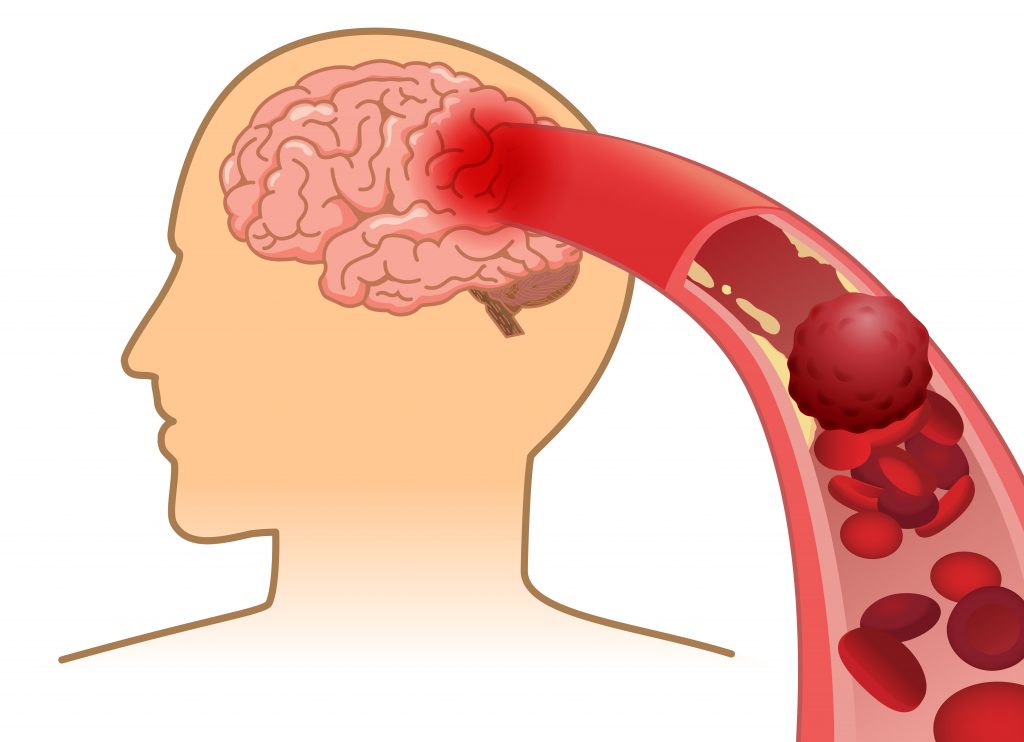

Ictus, con i trigliceridi elevati nel sangue il rischio ricaduta è più alto

Su Neurology il report della Tokyo Women’s Medical University